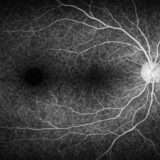

OCTとは?解析レポートの見方と活用ポイントを解説

CIRRUS OCTのGanglion Cell解析を徹底解説|GCL+IPLの意味とレポートの見方